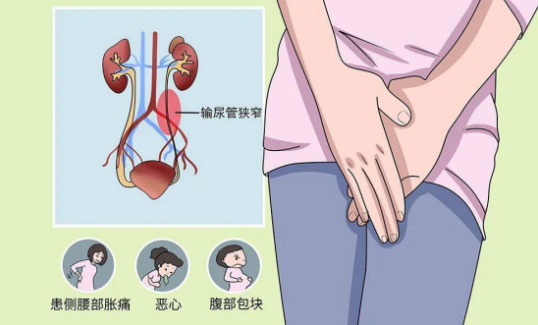

输尿管狭窄的临床表现取决于狭窄的程度和部位。轻度狭窄可能无明显症状,仅在体检或影像学检查时偶然发现。严重狭窄可表现为患侧腰部胀痛、肾积水、尿路感染、肾功能损害等。部分患者可能出现血尿、尿频、尿急、尿痛等症状。

输尿管狭窄是指输尿管管腔的局限性缩窄,导致尿液引流不畅,引起肾积水和肾功能损害。输尿管狭窄可发生在输尿管的任何部位,常见于肾盂输尿管连接部、输尿管中段和输尿管膀胱连接部。输尿管狭窄的程度和长度各不相同,轻者可能仅表现为输尿管轻度扩张和肾积水,重者可导致完全性梗阻和肾功能丧失。

先天性输尿管狭窄是由于胚胎发育异常所致,常见于肾盂输尿管连接部狭窄和输尿管膀胱连接部狭窄。肾盂输尿管连接部狭窄可能与肾盂输尿管连接部的肌肉发育不良、神经支配异常或输尿管瓣膜形成有关。输尿管膀胱连接部狭窄可能与输尿管末端的肌肉结构异常、膀胱输尿管反流或先天性巨输尿管症等有关。